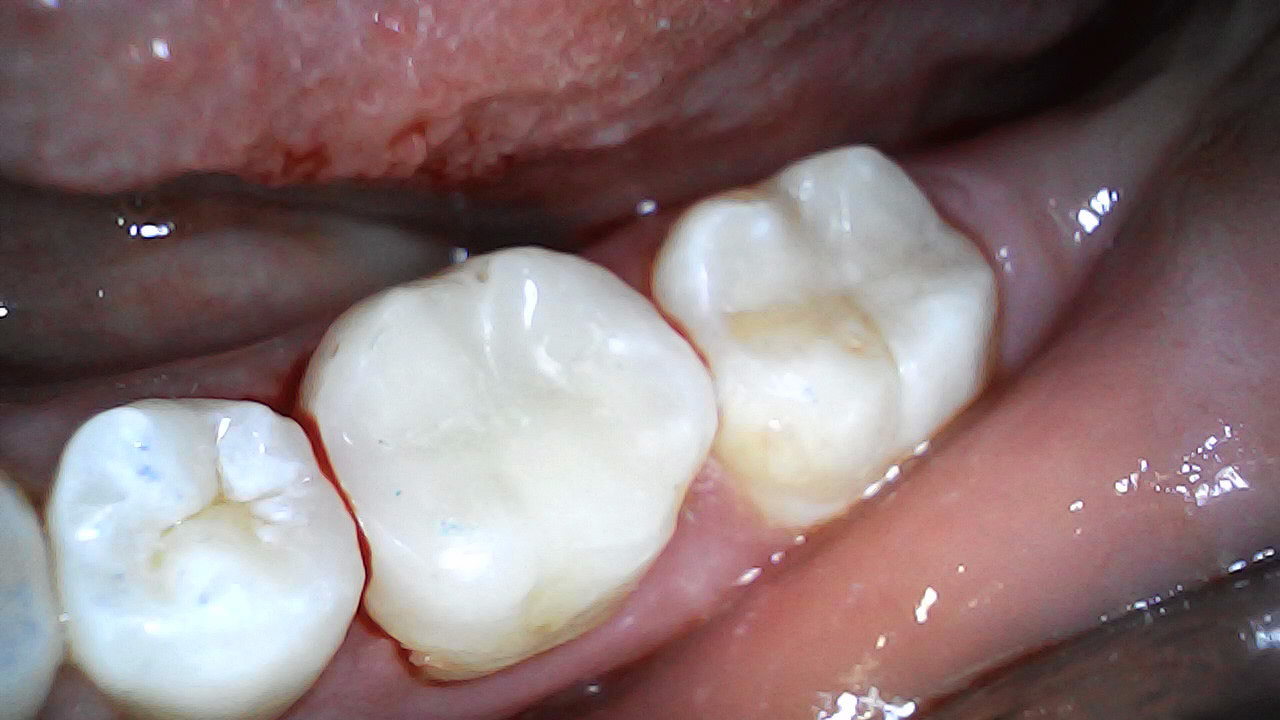

16 - 17 Pre-op